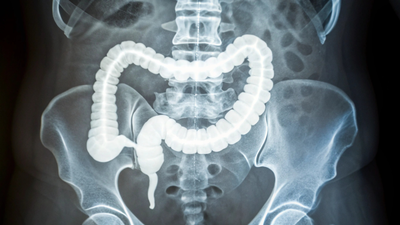

Why a stiffer colon is raising alarms as colorectal cancer appears earlier: How to identify it

Colorectal cancer used to be thought of as a disease of older age, striking mostly after 50, but over the past few decades, cases-and deaths in that group have dropped thanks to widespread screening like colonoscopies. But now—early-onset colorectal cancer, which hits before age 50, accounts for about 12% of all diagnoses in the U.S. since 2020. Rates have climbed sharply, with no single culprit fully explained yet.Many point to modern lifestyles: diets heavy in processed foods, extra pounds around the middle, and environmental factors that keep the gut irritated over time. This chronic swelling doesn’t cause immediate pain but builds quietly—setting the stage for trouble. Projections suggest these numbers could double by 2030, especially among those in their 20s to 40s, pushing doctors to rethink when to start checks.

A recent study sheds light on why colorectal cancer is showing up more often in younger adults, pointing to a stiffer colon as a potential early warning sign. Driven by years of low-grade inflammation—this tissue hardening seems to create the perfect storm for tumors to take hold and grow faster. Experts behind the research hope these findings open doors to better screening and treatments tailored for people under 50.The early-onset samples stood out: much more rigid overall. Digging deeper, the team found thicker, longer strands of collagen, the protein that builds up during scarring. This collagen was more mature and neatly aligned, hallmarks of repeated inflammation leaving its mark. Gene tests confirmed it, showing ramped-up activity for collagen processing, new blood vessel growth—and ongoing immune responses in the younger patients’ tissues.

Here’s where it gets fascinating. Chronic irritation in the gut leads to scars that toughen the colon walls, similar to what happens in breast or pancreatic cancers. Cells don’t ignore this; they feel the squeeze through a process called mechanotransduction. Mechanical stress flips switches inside cells, sparking biochemical signals that tell them to divide and spread.To prove the point, scientists grew colorectal cancer cells on surfaces mimicking different hardness levels. On stiffer ones, cells multiplied quicker. They even built 3D organoids—mini tumor models—from patient cells, and those on rigid bases ballooned larger and faster. This suggests a stiff environment doesn’t just let cancer thrive; it might nudge normal cells toward malignancy in the first place.